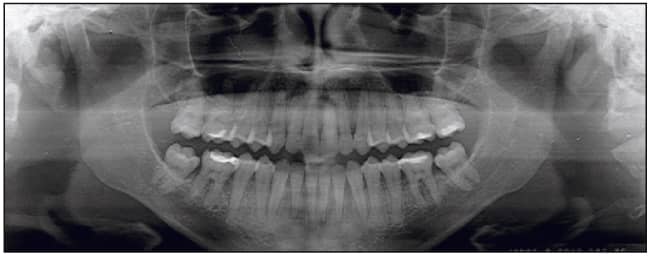

The patient, a 26-year-old female, presented with a chief complaint that she did not like her smile and was unable to bite with her front teeth. She presented with a concave profile due to an apparent midface deficiency and mandibular prognathism. She had a Class III anterior open bite malocclusion, confirmed by the cephalometric analysis (Figures 2 to 4).

The posterior discrepancy was eliminated by extraction of the existing three third molars. Leveling and aligning took 6 months with the use of .014 and .016 Sentalloy archwires. Interferences to mandibular adaptation were eliminated by creating a posterior open bite. Mandibular adaptation occurred within 8 weeks as the anterior open bite closed and a Class I relationship was established (Figures 5 and 6).

During the next 8 months of treatment, the occlusal plane was successfully reconstructed (tipped down in the front and steepened). Detailing ensured a stable functional occlusion. The patient was debonded and instructed to indefinitely wear an upper and lower thermoformed retainer a minimum of three nights per week (Figures 7 to 12).